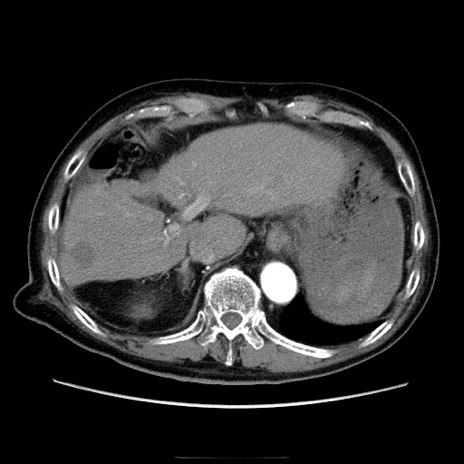

症例21(横断像)

【症例】70歳代男性

【主訴】腹痛

【現病歴】肝硬変・肝細胞癌にてかかりつけの方。約9時間前に食後より腹痛出現。症状が徐々に増悪し、嘔吐出現したため来院。

【既往歴】肝硬変、肝細胞癌(RFA、TACE後)

【身体所見】意識清明、表情苦悶様、BT 36℃、BP 129/78mmHg、P 88bpm、SpO2 97%(RA)、右上腹部から心窩部にかけて圧痛あり、反跳痛なし、筋性防御あり。

【データ】WBC 5800、CRP 0.16